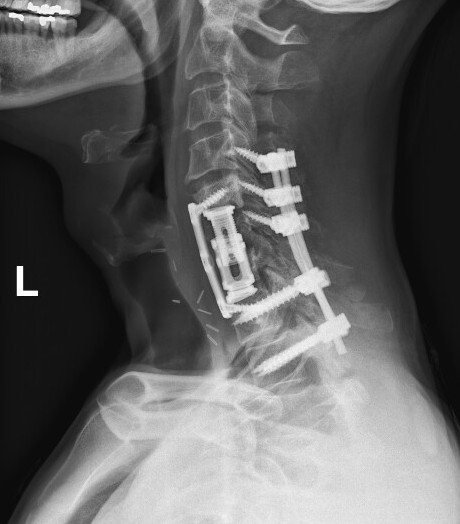

Cervical Spine Revision Surgery

Revision of a cervical spine surgery can be needed for a variety of reasons: failure for bones to fuse (cervical pseudoarthrosis), malposition or failure of implanted hardware, inadequate decompression of the spinal cord or nerve roots, new or persistent neck pain or cervical radiculopathy or myelopathy symptoms, degeneration of neighboring spinal segments, infection, spinal instability, and others.

Management options for a failed cervical surgery might include ACDF, cervical corpectomy, CORUS cervical fusion, or posterior cervical fusion, among others. Each of these options has benefits and drawbacks. The right surgery for you will depend on your symptoms, your previous surgery, the number of spinal levels affected, and factors related to your medical history, age, smoking status, and spinal anatomy.